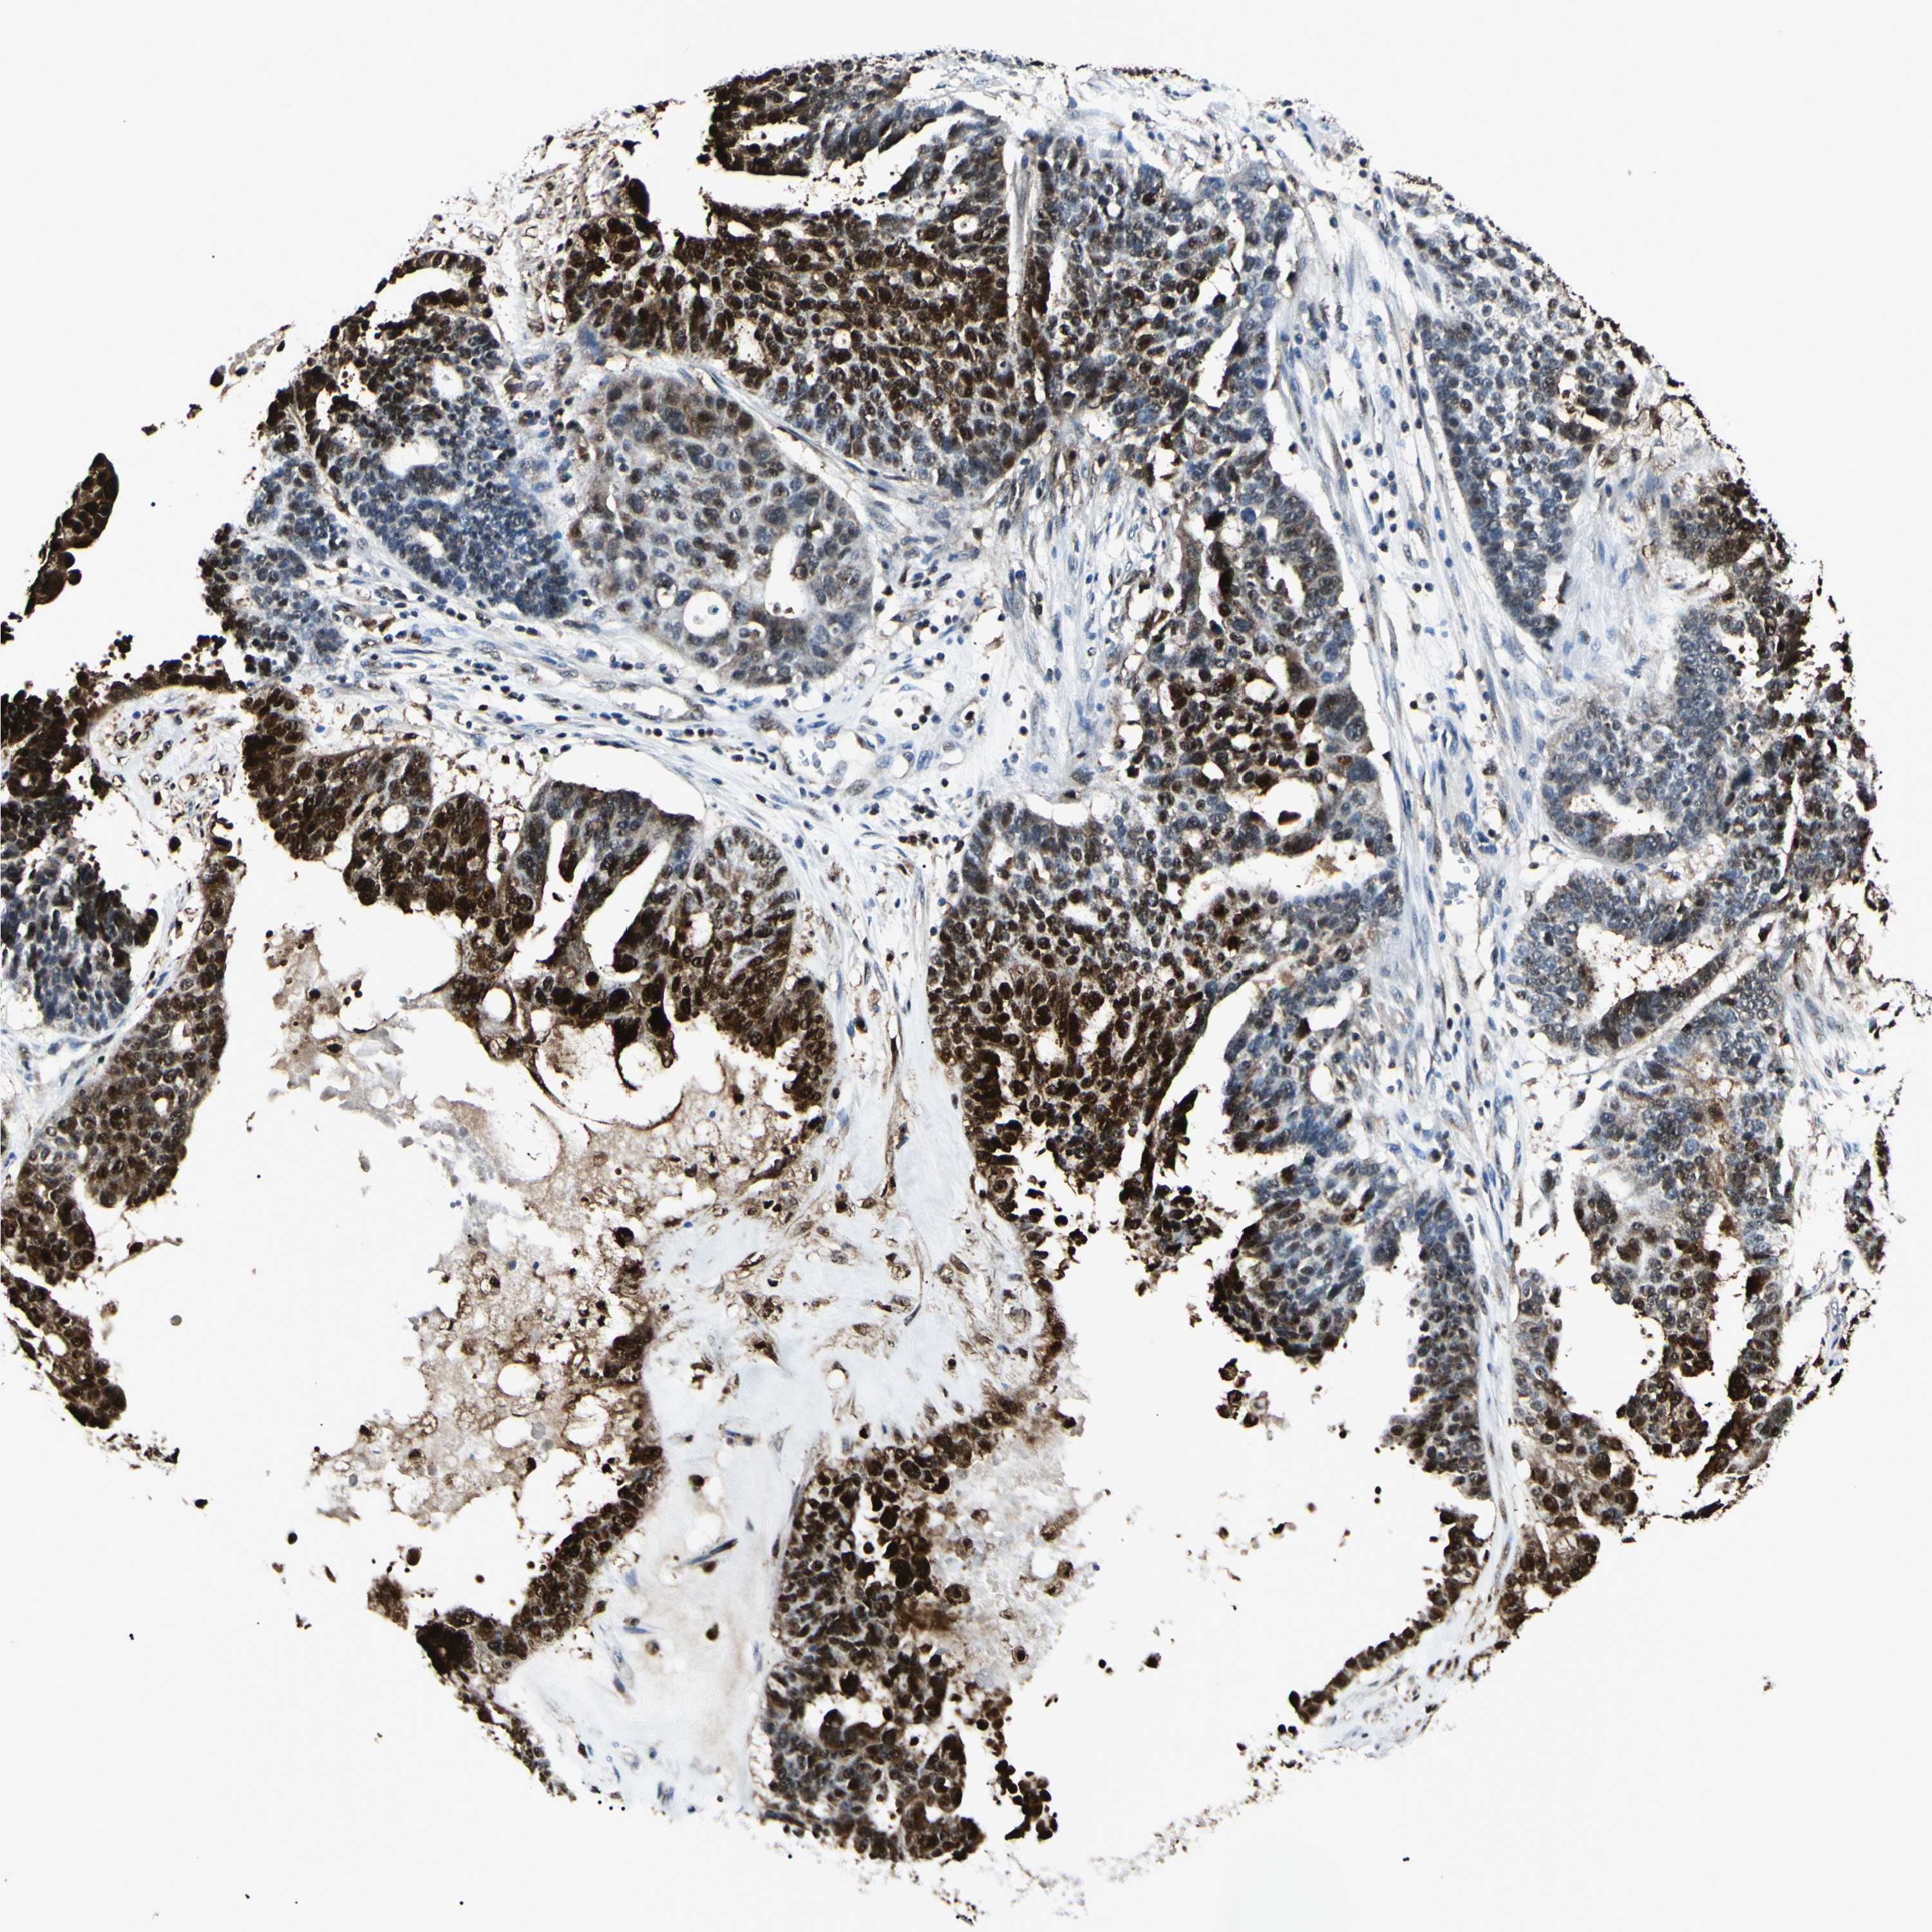

OVARIAN CANCER - Protein expressioni

A mouse-over function shows sample information and annotation data. Click on an image to view it in a full screen mode. Samples can be filtered based on level of antibody staining by selecting one or several of the following categories: high, medium, low and not detected. The assay and annotation is described here.

Note that samples used for immunohistochemistry by the Human Protein Atlas do not correspond to samples in the TCGA dataset.

Antibody stainingi

Antibody staining in the annotated cell types in the current human tissue is reported as not detected, low, medium, or high, based on conventional immunohistochemistry profiling in selected tissues. This score is based on the combination of the staining intensity and fraction of stained cells.

Each image is clickable and will lead to virtual microscopy that enables deeper exploration of all samples and also displays staining intensity scores, fraction scores and subcellular localization as well as patient and tissue information for each sample.

Antibody HPA073644

Staining

High

Medium

Low

Not detected

Cystadenocarcinoma, serous, NOS